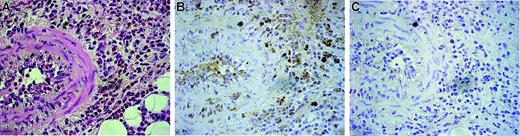

As shown in Figure 1, peripheral eosinophils from CSS patients expressed endogenous DDR1. The DDR1-positive percentage of CSS patients was significantly higher than that of asthma patients and healthy volunteers (Figure 1A-B). The total amount of DDR1 protein was also higher per 1 × 107 eosinophils in CSS patients, and the proportion of cells expressing the DDR1b isoform was also considerably higher in the eosinophils of these patients (Figure 1C-D). There was no significant difference in the concentrations of β1 integrin and another collagen receptor among the 3 groups. Immunohistochemical analysis revealed that the eosinophil staining in the blood vessels and in the wall of the blood vessels was positive for DDR1. Tissue-infiltrating eosinophils also stained positive for DDR1 (Figure 2).

Immunohistochemical analysis of DDR1 expression in the biopsied tissue of a CSS patient. Original magnification, × 350. (A) Hematoxylin-eosin staining. (B) Stained with the DDR1 antibody. (C) Negative control for the DDR1 antibody. Cells were stained with hematoxylin. Images were captured with an Olympus U-PMTVC microscope (Olympus, Tokyo, Japan) with a UPlan Apo 20×/0.80 NA objective lens, and an Olympus DP11-N. Images were captured with Adobe Photoshop 7.0 (Adobe Systems, San Jose, CA).

Immunohistochemistry

Biopsied tissues that were obtained from 3 CSS patients were examined by immunohistochemical staining for DDR1 by using a rabbit anti-DDR1 antibody (Santa Cruz Biotechnology) and were visualized by employing the DAB method as described previously.19 Sections 4 μm thick were mounted on poly-l-lysine–coated slides, dewaxed, and washed in Tris-buffered saline (pH 7.4) for 10 minutes. For optimal antigen retrieval, the sections were pressure cooked in 0.01 M citrate buffer (pH 6.0) for 90 seconds. Endogenous peroxidase activity was blocked using a 3% hydrogen peroxide solution in methanol for 10 minutes. Following 2 washes in PBS with 1% saponin, the blocking reaction was performed as reported previously.20 The sections were incubated with a primary antibody solution for 2 hours at room temperature by using a 1:50 dilution of the antibody. The negative control slides were incubated with rabbit IgG (R&D Systems). A secondary biotinylated anti-Ig antibody (R&D Systems) was added, and the mixture was incubated for 30 minutes at room temperature. After washing, the sections were incubated with streptavidin conjugated with horseradish peroxidase (Amersham) and then rinsed with deionized water. The DAB substrate solution was added, and the mixture was incubated for 10 minutes. A brown-colored reaction indicated a positive result.